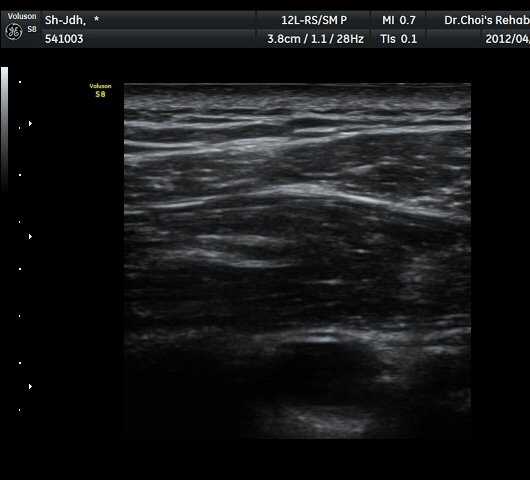

¾î±ú µÚ °üÀý¼ø °Ë»ç¿¡¼­ °üÀý¼ø Ç¥Ãþ¿¡ Àú¿¡ÄÚ ¼ö¾×Àú·ù°¡ °üÂûµÊ(»çÁø 4).

ŽÃËÀÚ¸¦ Á» ´õ µÚ·Î À̵¿ÇÏÀÚ °üÀý¼ø ³»Ãø °¡½Ã°üÀý¿À¸ñÆÐÀÓ(spinoglenoid notch)¿¡

¿øÇü¸ð¾çÀÇ Àú¿¡ÄÚ ³¶Á¾ÀÌ °üÂûµÊ(»çÁø 5, 6).